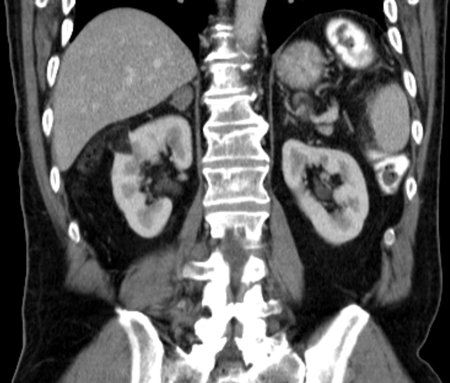

Case History: 60-year-old man with mild right side abdominal discomfort and hepatomegaly found to have large right renal mass during CT scan.